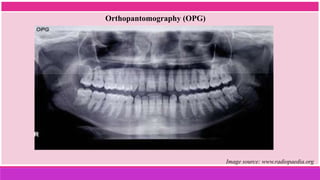

 Orthopantomography (OPG)

Orthopantomography (OPG)

Image source: www.radiopaedia.org